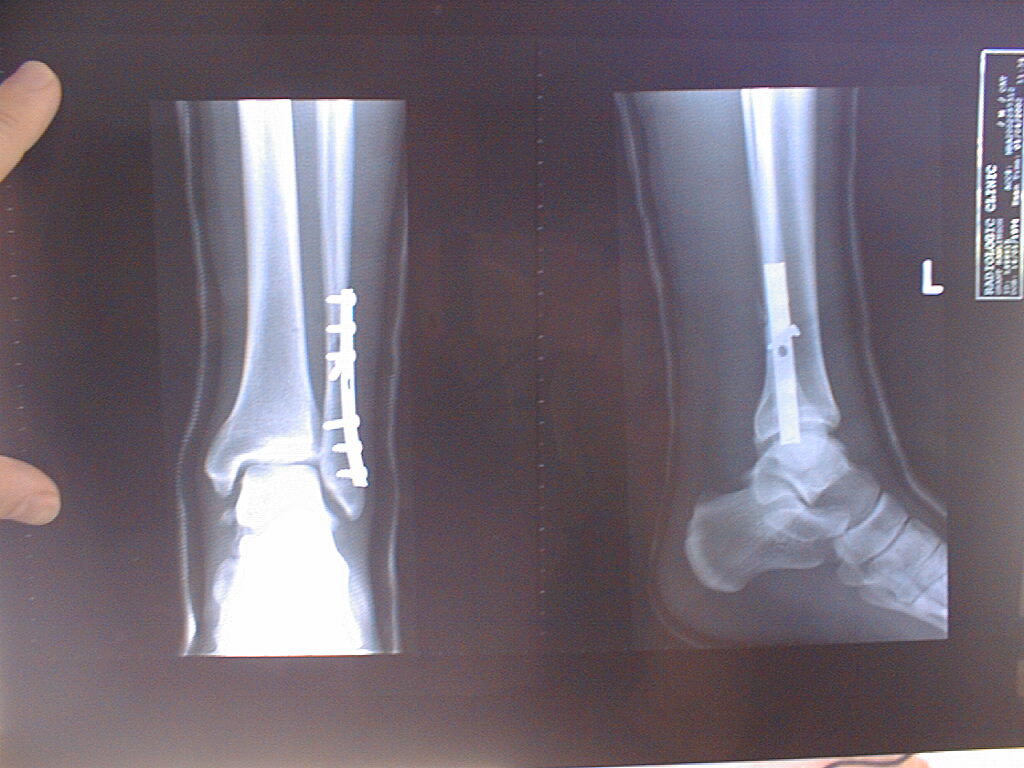

As sore as my ribs are, the most painful injury I can ever remember suffering was breaking my leg whilst playing in the Hong Kong Sevens in 2002. The thought of the pain that swamped me immediately following that injury, as my ankle dislocated and my fibula snapped still makes me feel a little nauseous and I hope I never get to repeat that sensation! Attached is an XRAY showing some of the plates and screws inserted into my ankle – which are still there.